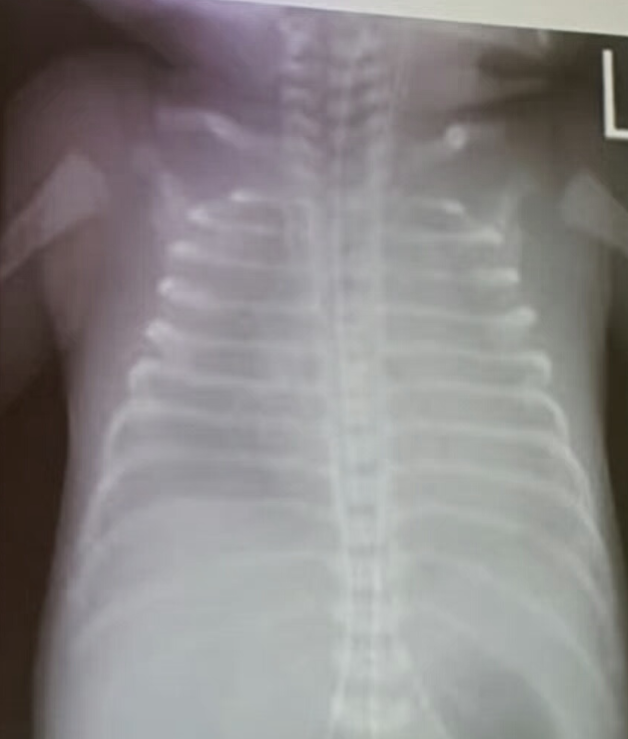

Case: Preterm Infant with Respiratory Distress

- Preterm 29 weeks gestation C/S delivery showed severe respiratory distress soon after birth - RDS

- Air bronchograms

There is a homogeneous opacification of both lungs with white-out lungs - (1 .field (grounds glass appearance) and air bronchogram bilaterally

.The diagnosis is Acute Respiratory Distress Syndrome (ARDS) - (2

- .I- Massive blood transfusions Preterm 29-weeks gestation C/S delivery showed severe respiratory distress soon after birth. This chest x-ray was taken at the age of 6 hours.

- Q1: Write 2 abnormalities in the X-Ray?

- Q2: What is the likely diagnosis?

- Q3: Write 2 management steps.

Answers:

- Q1: Ground glass appearance, wide intercostal space.

- Q3: Mechanical ventilation, give Surfactant for lungs maturation.